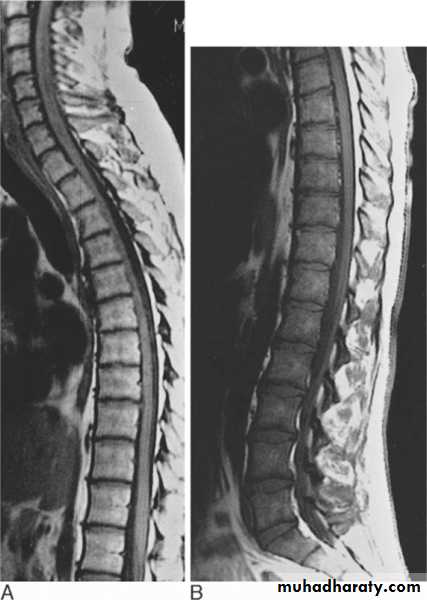

AT1-weighted images is one in which the contrast between tissues due mainly to their T1 relaxation propereties ,while in a T2-weighted image the contrast between tissues due mainly to their T2 relaxation propereties .

Most pathological processes show increase T1 and T2 relaxation times and these processes therefore appear lower in signal (blacker )on a T1 –weighted scan and higher in signal (whiter ) on a T2 –weighted scan than the normal surrounding tissue

T1 weighted images used for anatomical details (normal stracture )and T2 weighted images used for pathological processesMRI SCANNER